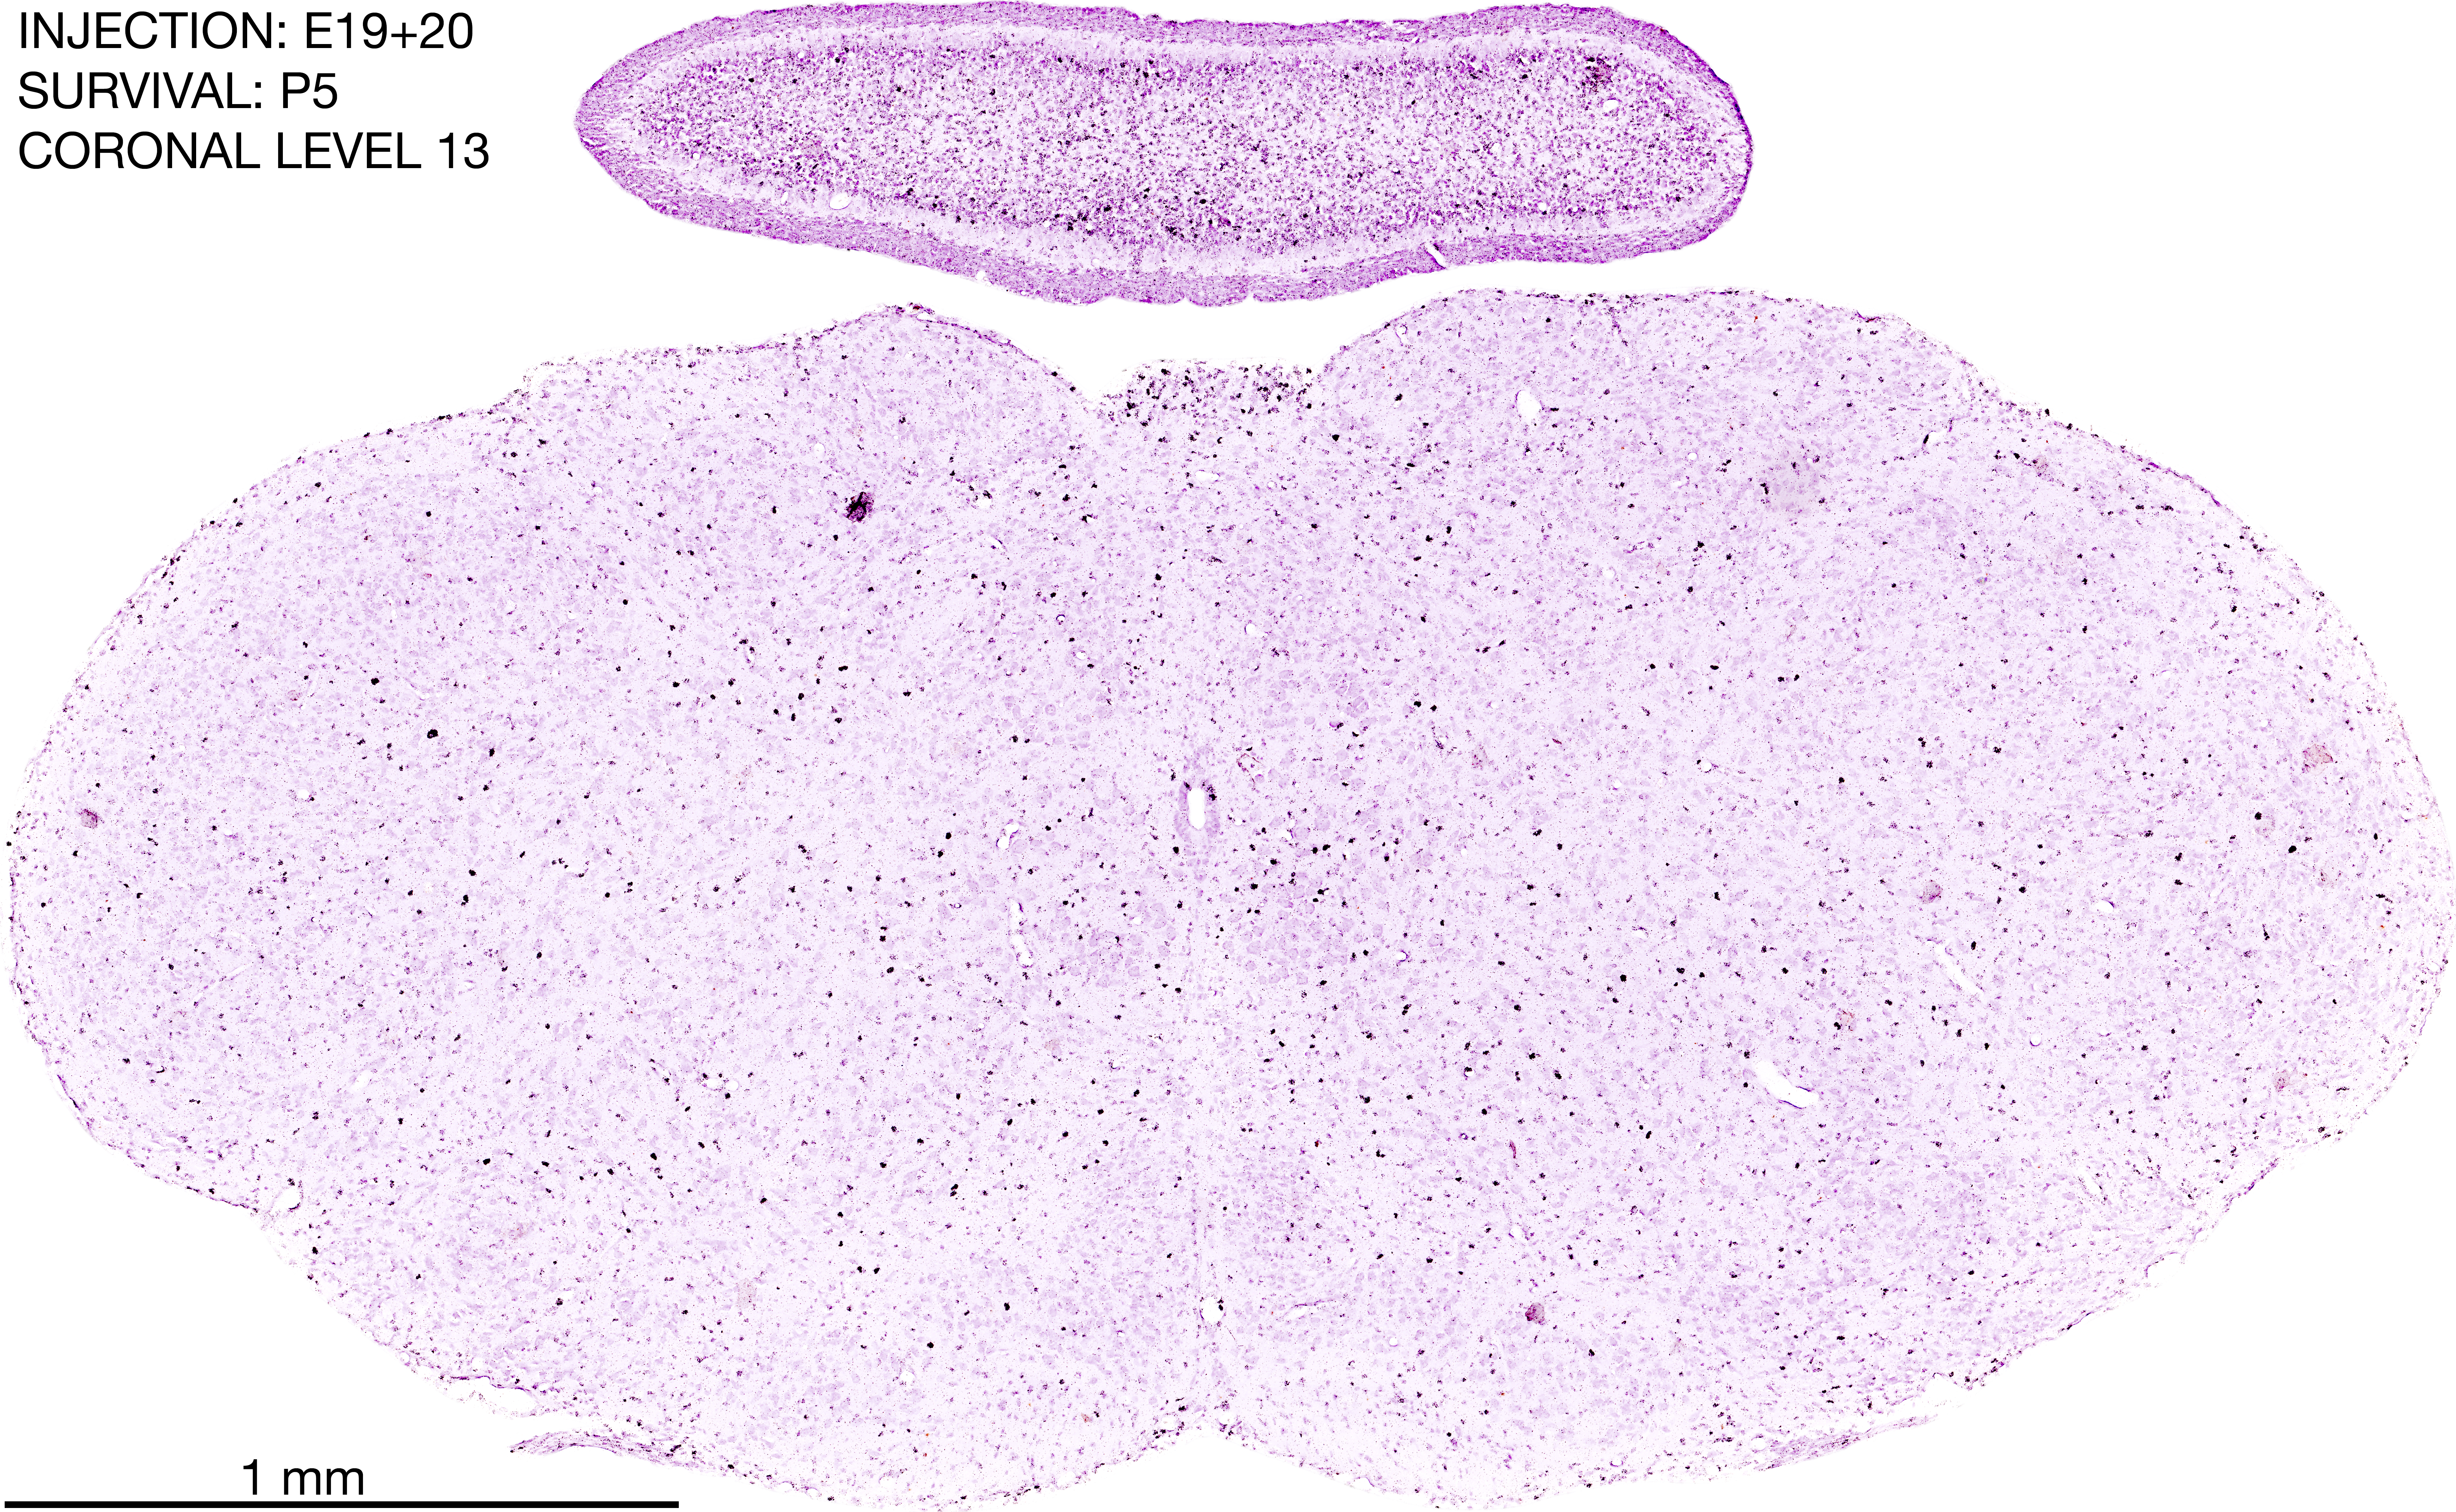

E19+20 P5 Survival The images below are from the brain of a rat that was exposed to tritiated thymidine on E19+20 and survived to P5. Download: Large | High Res Download: Large | High Res Download: Large | High Res Download: Large | High Res Download: Large | High Res Download: Large | High Res Download: Large | High Res Download: Large | High Res Download: Large | High Res Download: Large | High Res Download: Large | High Res Download: Large | High Res Download: Large | High Res Download: Large | High Res Download: Large | High Res Download: Large | High Res Download: Large | High Res Download: Large | High Res Download: Large | High Res Download: Large | High Res Download: Large | High Res Download: Large | High Res Download: Large | High Res Download: Large | High Res Download: Large | High Res Download: Large | High Res Download: Large | High Res Download: Large | High Res